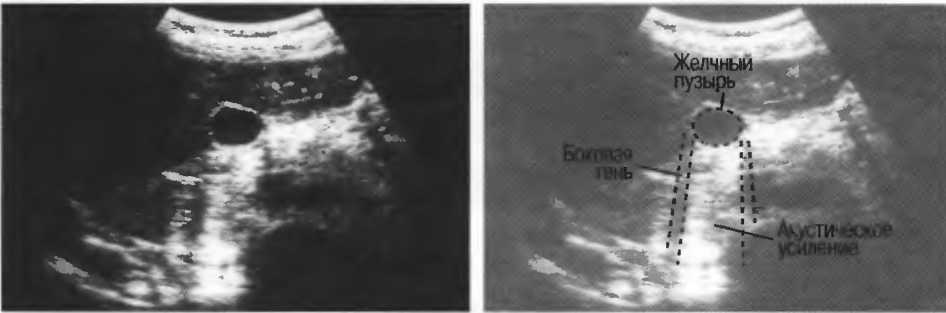

Частота и разрешающая способность

Чем выше частота ультразвукового излучения, тем выше разрешающая способность. Это означает, что при использовании более высокой частоты возможна визуализация более мелких структур. Одновременно проникающая способность ультразвуковой волны в ткани становится меньше. Сканирование, таким образом, является компромиссом; при этом используется максимально высокая частота, достаточная для проникновения на заданную глубину (рис. 11).

Рис.11. Изображение матки при использовании датчиков разной частоты. Качество лучше оценивается при исследовании структур эндометрия. В наполненном мочевом пузыре определяются реверберации.